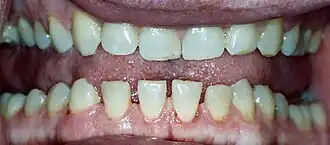

Acromegalia é uma doença que resulta da produção excessiva de hormona do crescimento após o fecho das placas de crescimento.[1] Na maior parte dos casos, o sintoma inicial é o crescimento das mãos e dos pés.[1] Pode também ocorrer crescimento da testa, maxilar e nariz.[1] Entre outros possíveis sintomas estão dores nas articulações, espessamento da pele, agravamento da voz, dores de cabeça e perda de visão.[1] Entre as possíveis complicações estão diabetes do tipo 2, apneia do sono e hipertensão arterial.[1]